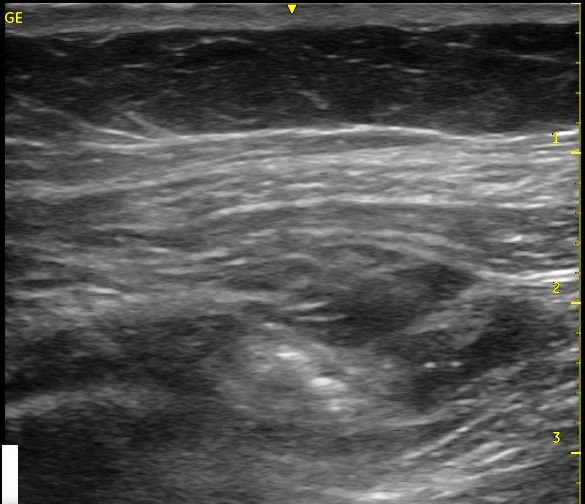

I always say that ultrasound should be used like a video, not just as a picture. The thin slice where the needle lies only gives you a very small view of what is happening within the tissues. If you are having trouble recognizing whether the spread is extending as it should, slide your probe to the ‘periphery of the spread’ where the architecture is still fully intact and visualize the spread from this location. You are starting from pristine architecture and visualizing the changes as you approach your injection site, and you will be able to see whether the local is going where you want it to go or not. Start from the pristine image and slide back toward your original position to see the changes that occur. This may be enough information for you to confirm that you are, in fact, in the correct position, and you can return to your bolusing process. [nonmember]

[ismember]Keep the images that you saw in your mind, however, so that after you begin to inject later, you will know which black areas have gotten larger if there are more than one. You have likely added local where it is supposed to go as well as in places where it is not supposed to go, and you want to know which region is expanding. This will allow you to know whether you should stay where you are injecting or withdraw or advance your needle. Either way, return to the peripheral position and visualize the changes as you continue bolusing. You will want to see a thicker and thicker black line appear between the muscle layers as you continue to inject. This is proof that your bolus is within the plane and clearly spreading above (and below since you can slide to see this same change occur on the other side of your needle) your injection site. Leaving your catheter in the space you created should allow you to maintain the size of the ‘puddle’ of local anesthetic that you have just created. You can make adjustments to your needle if you begin to see that local is clearly amassing above of below your target, and this will allow you to salvage your nerve block. This technique of ‘watching from afar’ is worth performing even in situations where the spread is obvious from the start. It will give you a better idea of the breadth of your spread, and it is a good exercise to help you to recognize and appreciate more the 3-D anatomy from the 2-D image. You can do this with other nerve blocks as well! It will help you to recognize how far to the left and right of the beam that your local spreads with your individual technique.

Look at the images below. They appear to be a series of pictures arranged from the beginning of an injection to the end. In fact, no further injection is added. The first image is taken at the periphery of a TAP block, and the subsequent images are taken as the probe is slid closer to the center of the injection. They confirm that the needle is adequately placed within the appropriate plane though the central position is a bit difficult to interpret.